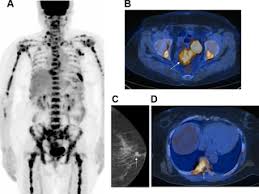

Fdg Pet Pet Ct And Breast Cancer Imaging Radiographics from pubs.rsna.org A breast pet scan is often very specific and sensitive and is approved for patients. It's an effective imaging test for finding cancer and learning its stage. Bone scans, positron emission tomography (pet), and computed tomography (ct) all continue to be employed alone or in combination for the detection of breast cancers suspected to have spread. Breast positron emission tomography (pet) scan is an imaging test that uses a tracer (radioactive substance) to look for symptoms of breast cancer. Pet scan is a type of test that may be used in cancer treatment. Pet scans can be used to determine how much cancer is in a person's body and how far the cancer has spread, which is called staging. It can be done along with a ct scan. Pet scans can be useful for evaluating people after breast cancer has already been diagnosed, in a number of different ways:

The test has only a limited ability to detect small tumors. Pet scan for breast cancer a positron emission tomography (pet) scan is an imaging test that uses a radioactive substance (called a tracer) to look for potential spread of breast cancer. In some instances, cancers may not show on the scan. Combining a pet scan with an mri or ct scan can help make the images easier to interpret. Pet scans can be used to determine how much cancer is in a person's body and how far the cancer has spread, which is called staging. This tracer can help identify areas of cancer that an mri or ct scan may miss. With cancer cells, they appear as bright spots due to its higher metabolic rate compared to normal cells. However, the pet scan uncovers every unusual activity in the body and is more sensitive than any other existing imaging test. Pet/ct scan can accurately localize lymph node metastasis and help to monitor the response to chemotherapy. Breast positron emission tomography (pet) scan is an imaging test that uses a tracer (radioactive substance) to look for symptoms of breast cancer. Pet scans can also help to assess whether metastatic breast cancer is responding to the treatment. Pet scans are not used to screen women for breast cancer. Pet/ct scans using axumin tracer, approved by fda last year and newly approved by medicare in some areas, are starting to be done at different locations.

The Clinical Utility Of Fdg Pet Ct In Follow Up And Restaging Of Breast Cancer Patients Sciencedirect from ars.els-cdn.com Pet scan is a type of test that may be used in cancer treatment. A ct scan produces multiple images, providing a detailed picture of the internal anatomy, including the location of cancerous growths. If you have a large breast cancer, your doctor may order a ct scan to assess whether or not the cancer has moved into the chest wall. This substance is often called a tracer, because it helps reveal cancer in the body. It is similar to a pet scan, but it uses a different radioactive substance that settles in areas of change in the bones. For cancer, pet is especially useful as it can scan the entire body and pinpoint both a primary tumor and areas of metastasis (where the cancer has spread). In some instances, cancers may not show on the scan. When breast cancer cancer spreads.

It is common for patients to receive a diagnosis for cancer of unknown primary. Types of cancer detected and treated. Its supposed to be more sensitive/specific than naf and other older scans, and comparable i think to choline or acetate (lots of studies and info on the web) and. With that being said, not all cancers can be detected by pet. A breast pet scan is often very specific and sensitive and is approved for patients. Although it is not appropriate for all patients with breast cancer, fdg pet/ct can have an important clinical effect for appropriate patients. Normally, a pet scan is not used for breast cancer screening. With cancer cells, they appear as bright spots due to its higher metabolic rate compared to normal cells. When breast cancer cancer spreads. Each has its own strengths. For cancer, pet is especially useful as it can scan the entire body and pinpoint both a primary tumor and areas of metastasis (where the cancer has spread). This test can help show if the cancer has spread to your bones. One example is a combined pet and ct scan (known as pet/ct), available in some centers.

Thus, pet/ct detected a primary breast mass and metastatic lymphadenopathy that mammography and ultrasonography failed to detect a finding not previously reported, to our knowledge. Mammograms take advantage of the fact that most of the female breast is fat tissue, so it's relatively transparent to the low doses of radiation used in mammography. One example is a combined pet and ct scan (known as pet/ct), available in some centers. Does anyone know if a ct scan can show breast cancer or colon cancer rather than the standard mammogram or colonoscopy? When breast cancer cancer spreads.

Mammograms take advantage of the fact that most of the female breast is fat tissue, so it's relatively transparent to the low doses of radiation used in mammography. Am wondering if all the while we are getting ct scans for lung cancer, is this also scanning for. This test can help show if the cancer has spread to your bones. Normally, a pet scan is not used for breast cancer screening. This radioactive tracer can help identify areas of cancer that an mri or ct scan may miss. In conclusion, this case shows that pet/ct can be utilized as an alternative method of diagnosing breast cancer in cases where conventional imaging modalities fail. The report of ct scan cannot be the basis of determining if a patient has cancer or not; A pet scan is often combined with a ct scan (known as a pet/ct scan). Right now, ct scans are not used routinely to evaluate the breast. This tracer can help identify areas of cancer that an mri or ct scan may not show. A breast pet scan is often very specific and sensitive and is approved for patients. Objectives bone is the most frequent site of breast cancer metastases.considering many breast cancer patients are old age,bone is likely affected by degenerative or inflammatory bone disease.recently pet/ct has become an alternative study which could provide an accurate and efficient tool for detection of primary and metastatic foci.the purpose of this study was to compare the accuracy between pet/ct and bone scan for detecting bone metastases in breast cancer. In a ct scan, you can see the broad pictures of all tissues and organs present in the body.